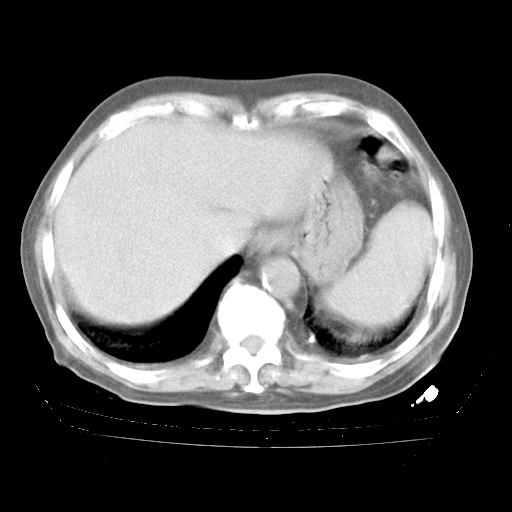

4月28日肺部CT——再次出现类似去年5月9日——透光度降低,“间质性”改变。

4月28日肺部CT——再次出现类似去年5月9日——磨玻璃样、间有“粟粒样”改变。

4月28日肺部CT